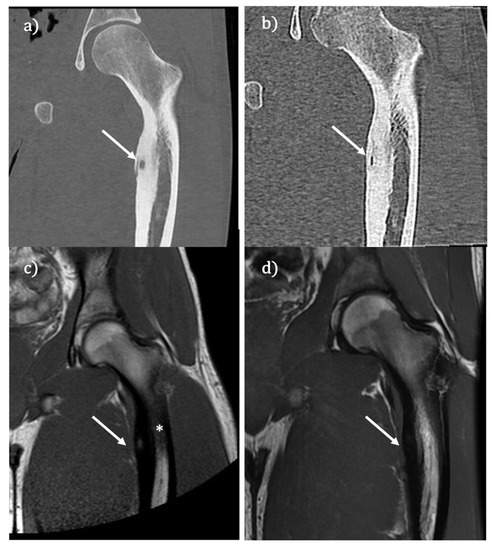

Post-Procedural Follow-Up of the Interventional Radiology’s Management of Osteoid Osteomas and Osteoblastomas

2. Osteoid Osteoma